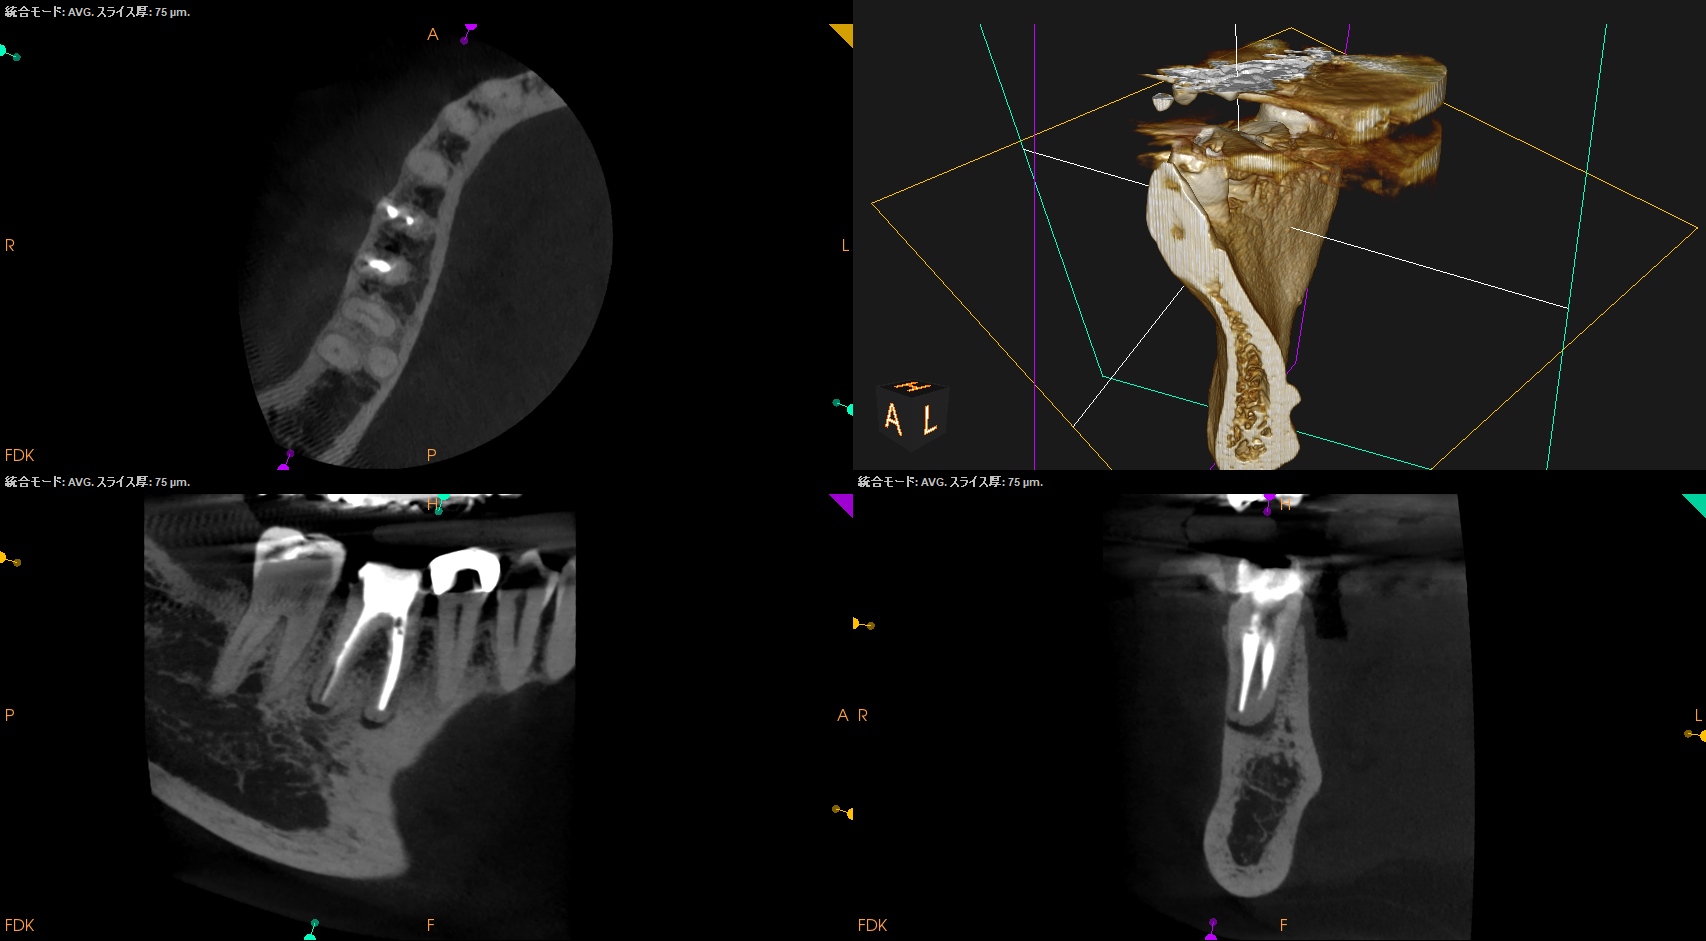

CBCT(2025.12.2)

MB

ML

D

M,Dの根尖部には病変がある。

またMもDも形成・根充が太くなされているので治療は成功率が低いであろう再根管治療ではなくApicoectomyだ。